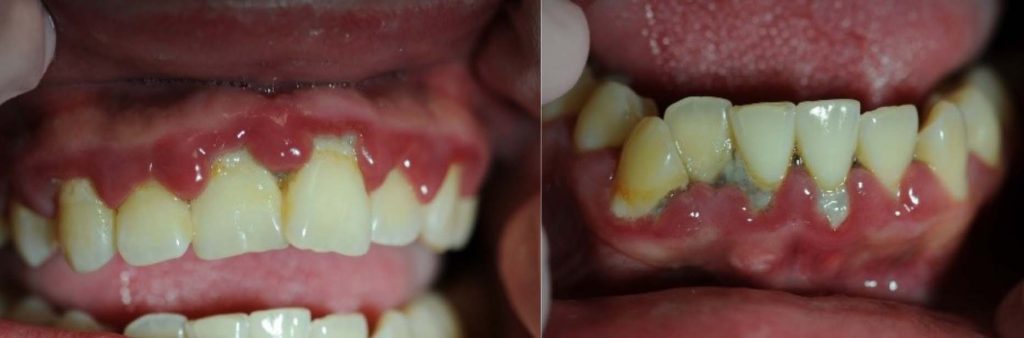

Appendix: Photo- and Radiographs of Periodontal Disease Associated With HIV

Photographs courtesy of Dr. Gwen Cohen Brown and the Dental Hygiene Department of New York City College of Technology

Figure 1: Patient with linear gingival erythema (LGE)

Figure 2: Patient with necrotizing ulcerative periodontitis (NUP)

Figure 3: Patient with linear gingival erythema (LGE) and necrotizing ulcerative periodontitis (NUP)

Figure 4: Patient with necrotizing ulcerative gingivitis (NUG)